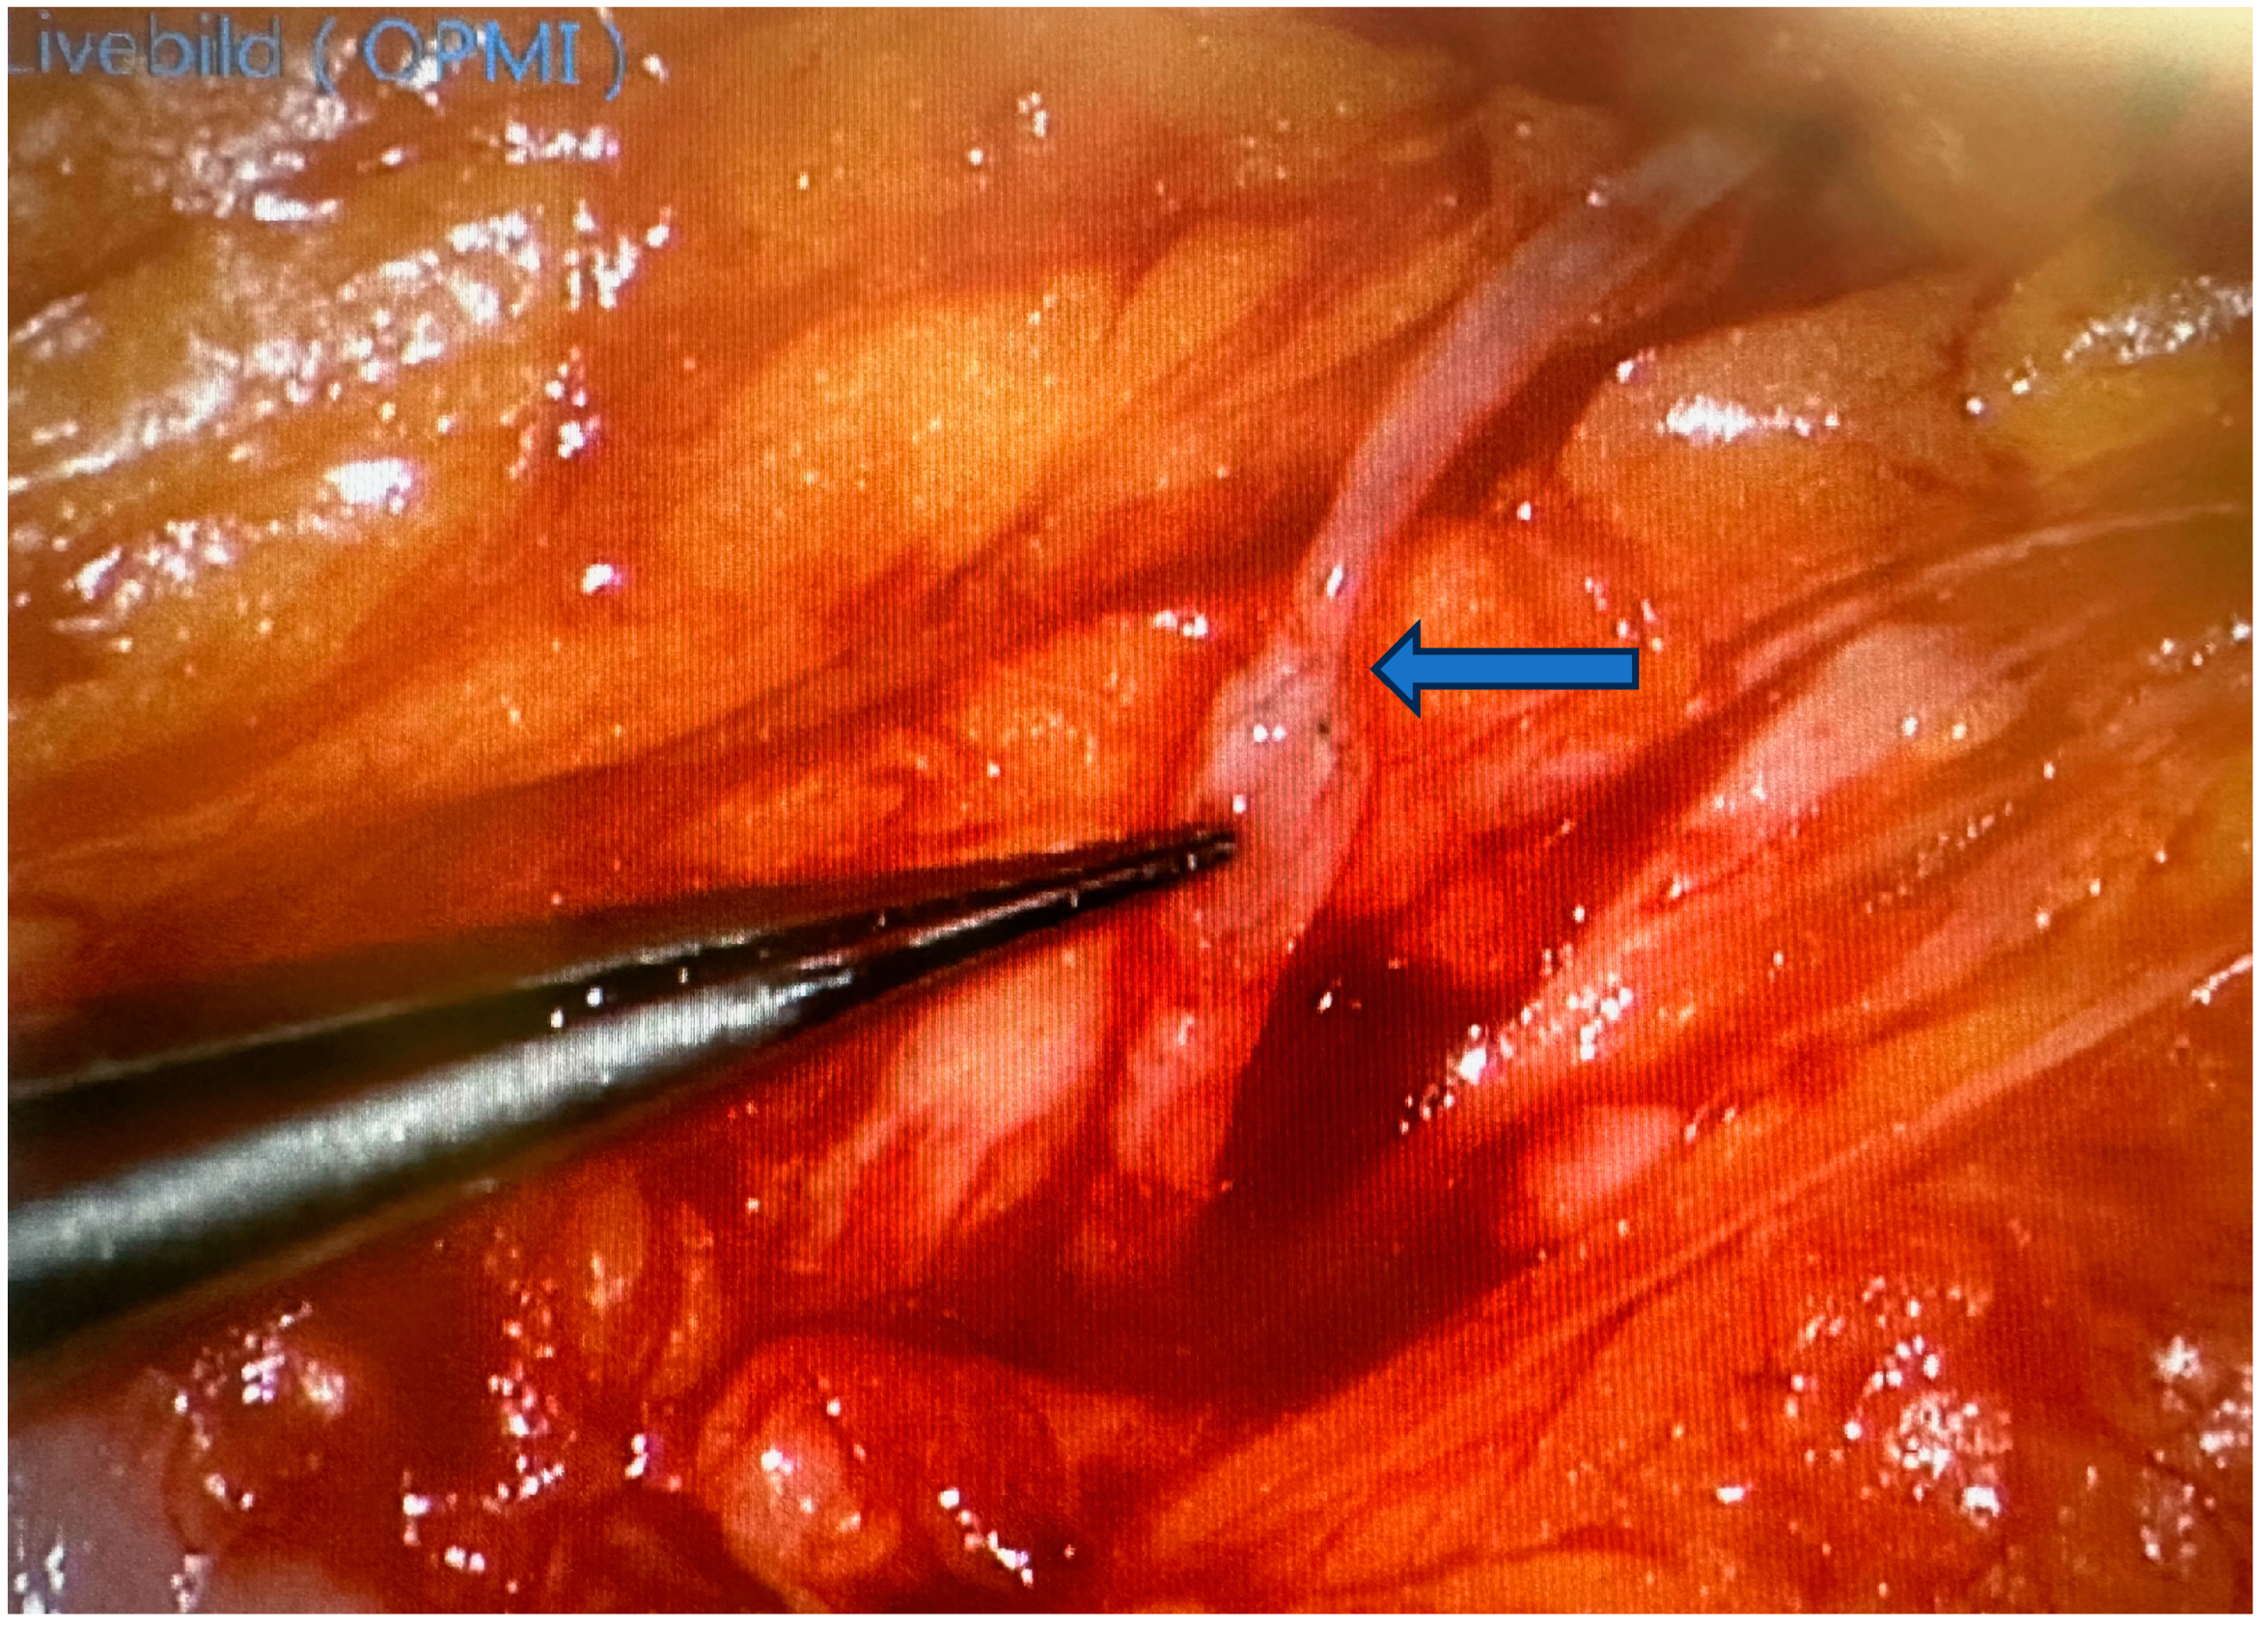

2. Robotic Microsurgery

3. Advances in Peripheral Nerve Surgery

3.2. Advances of Nerve Bridging and Transfer